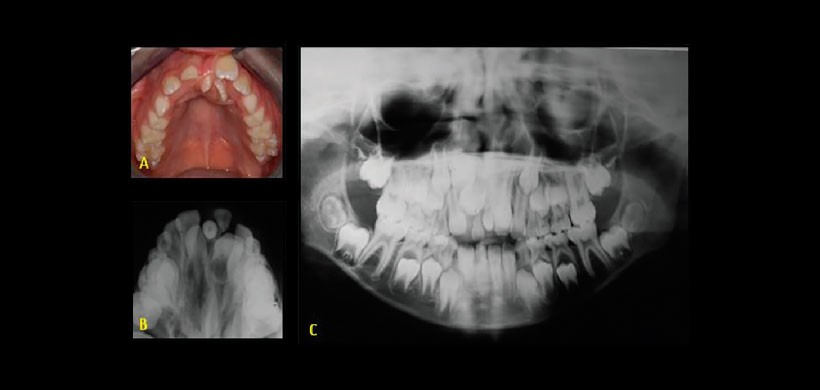

Fig 3. En la radiografía oclusal, panorámica y en los cortes tomográficos se aprecia la presencia de 2 dientes supernumerarios localizados a nivel medial del maxilar, ocasionando la impactación de las piezas 1.2, 1.1, 2.1, 2.2 y 2.3